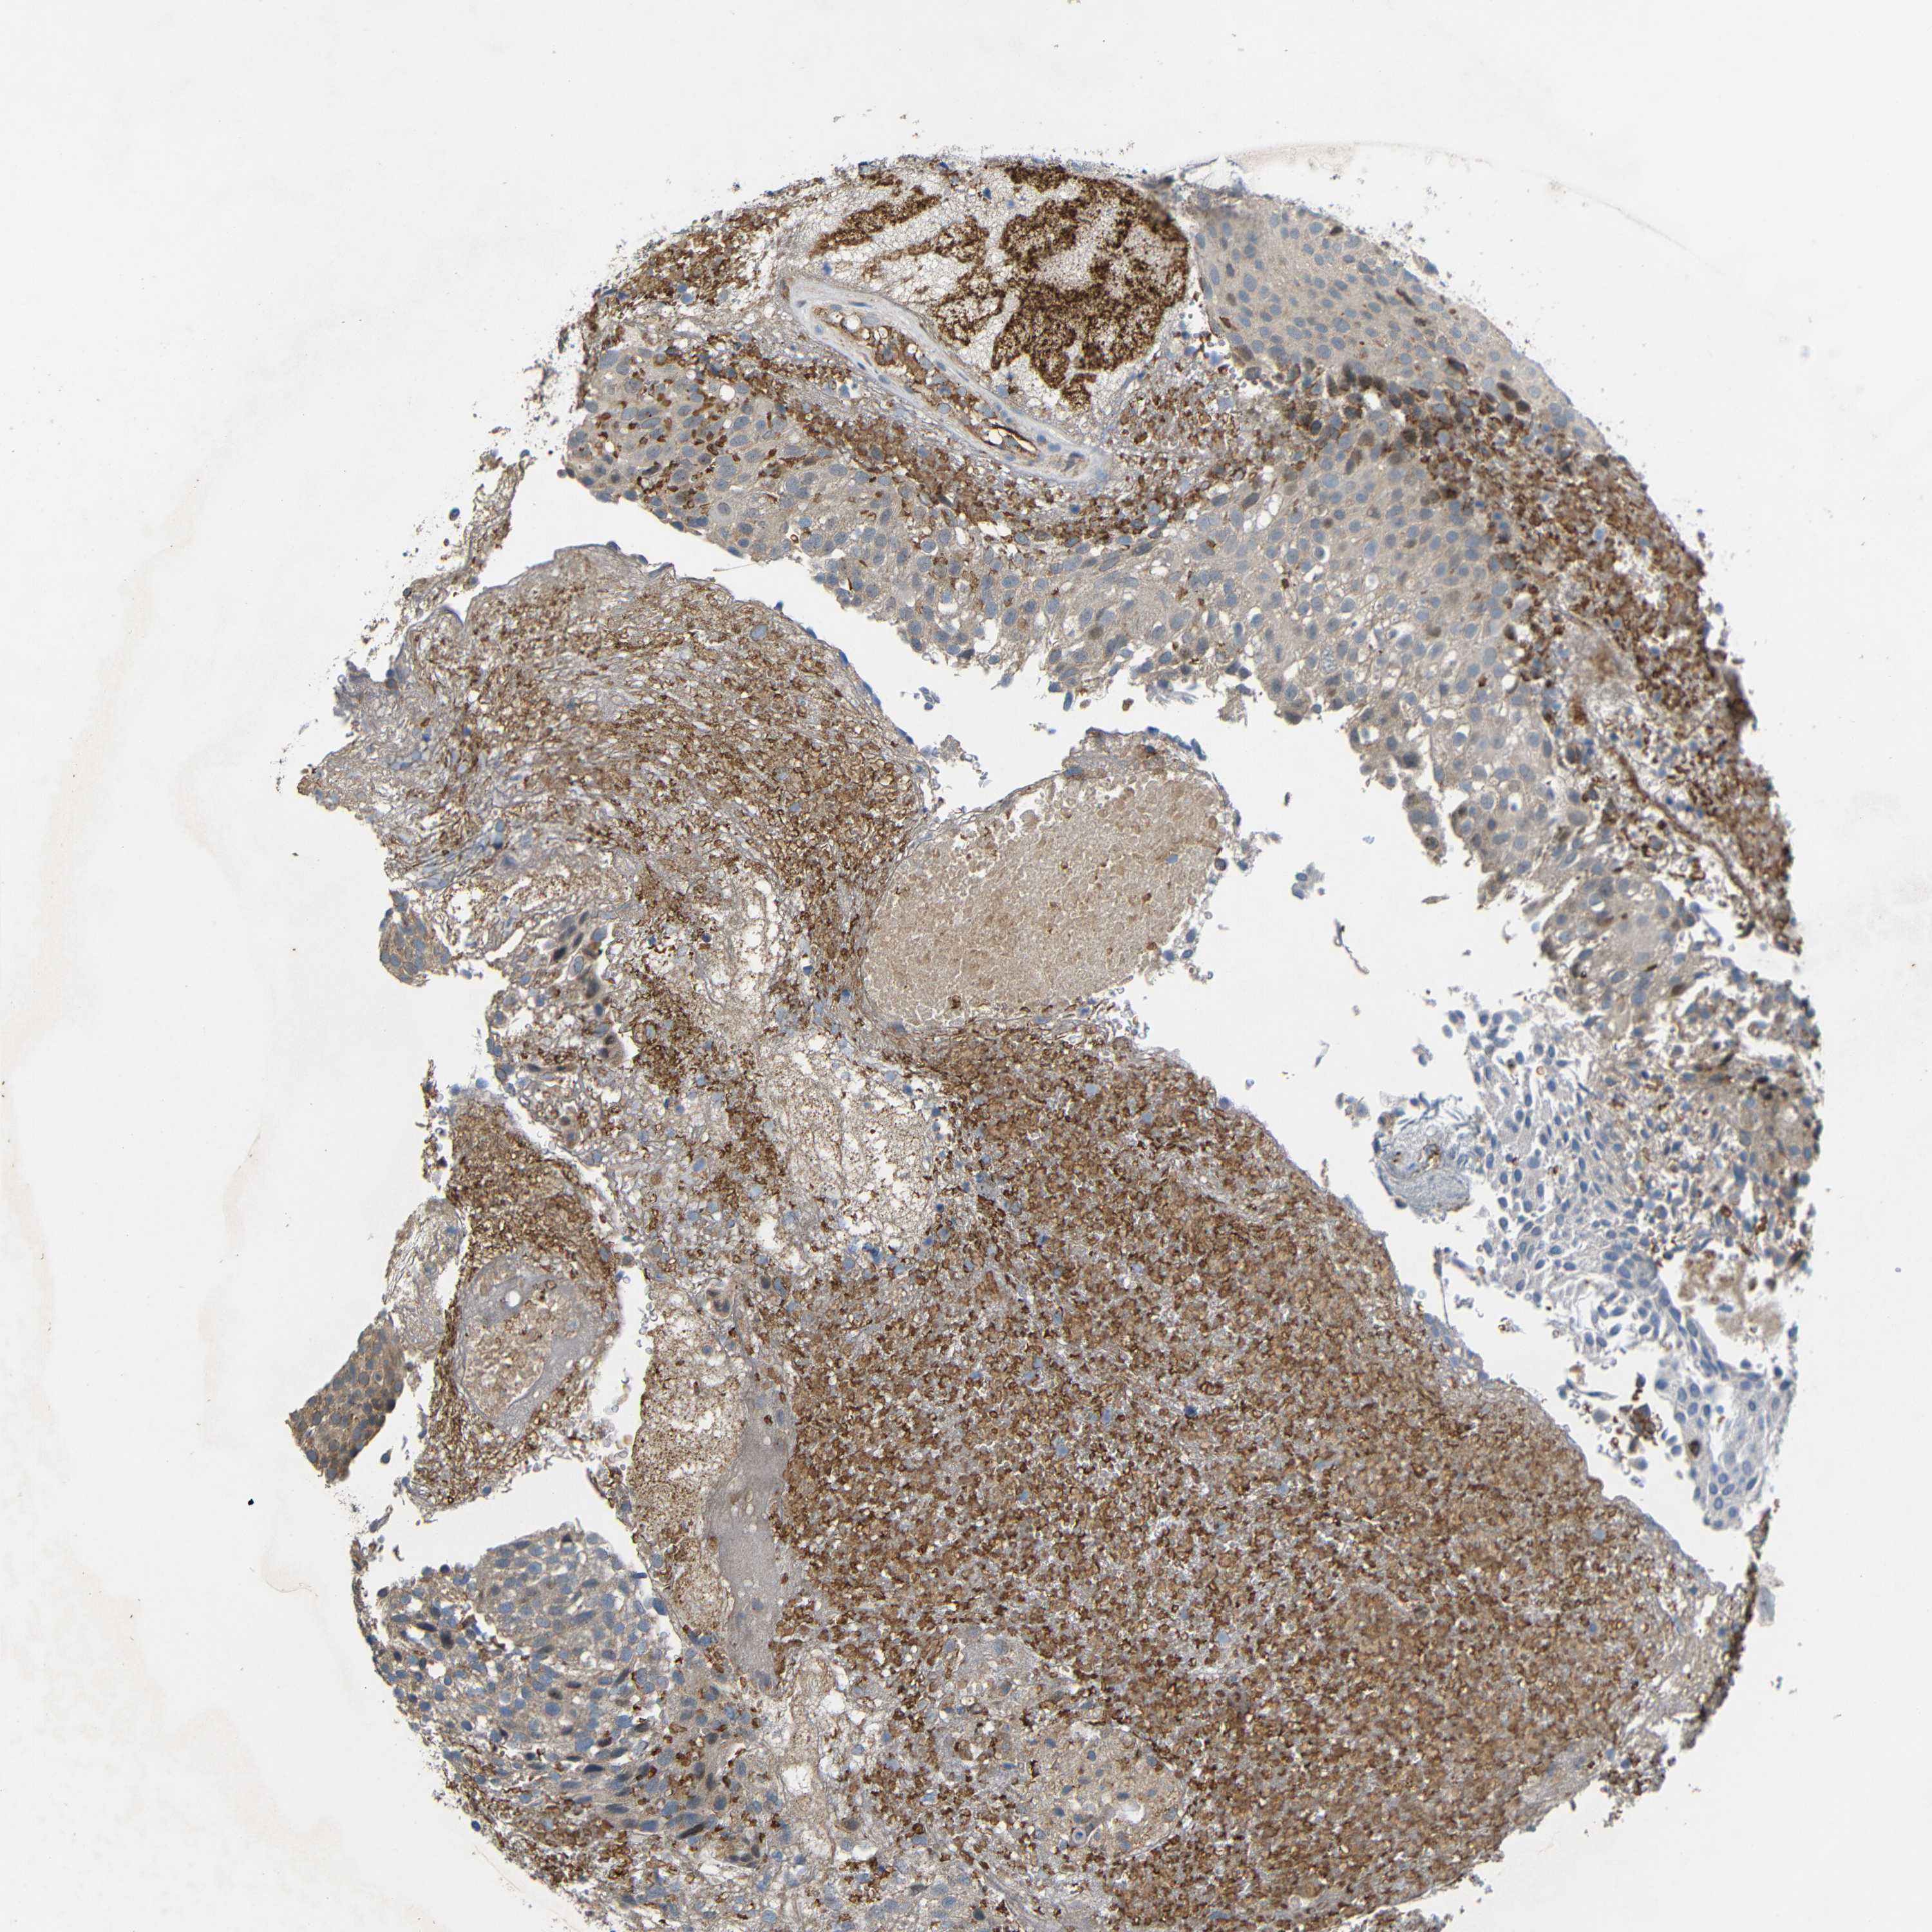

UROTHELIAL CANCER - Protein expressioni

A mouse-over function shows sample information and annotation data. Click on an image to view it in a full screen mode. Samples can be filtered based on level of antibody staining by selecting one or several of the following categories: high, medium, low and not detected. The assay and annotation is described here.

Note that samples used for immunohistochemistry by the Human Protein Atlas do not correspond to samples in the TCGA dataset.

Antibody stainingi

Antibody staining in the annotated cell types in the current human tissue is reported as not detected, low, medium, or high, based on conventional immunohistochemistry profiling in selected tissues. This score is based on the combination of the staining intensity and fraction of stained cells.

Each image is clickable and will lead to virtual microscopy that enables deeper exploration of all samples and also displays staining intensity scores, fraction scores and subcellular localization as well as patient and tissue information for each sample.

Antibody HPA012887

Staining

High

Medium

Low

Not detected

Intensity

Strong

Moderate

Weak

Negative

Quantity

>75%

75%-25%

<25%

None

Location

Nuclear

Cytoplasmic/membranous

Cytoplasmic/membranous,nuclear

Urothelial carcinoma, Low grade

Urothelial carcinoma, High grade